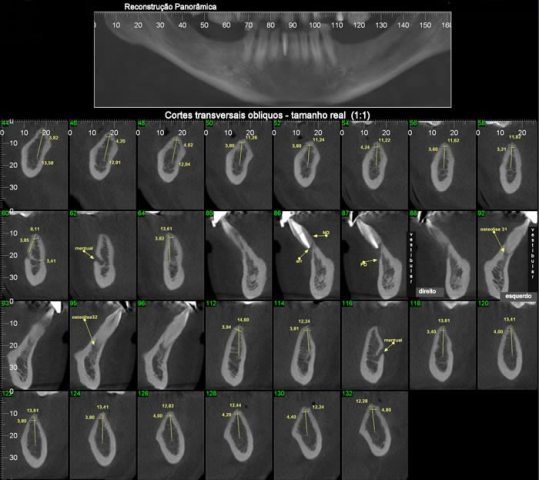

Os cortes transversais são cortes perpendiculares ao arco da maxila e mandíbula.

Na reconstrução panorâmica aparece uma régua no limite inferior que serve de localização para os cortes transversais.

Os cortes longitudinais são cortes no sentido vestíbulo lingual ou palatino, perpendiculares a uma reta traçada sobre o dente ou a área em questão.

Para verificar morfologia, quantidade e qualidade óssea. Também utilizada para avaliação das estruturas ósseas adjacentes aos implantes.